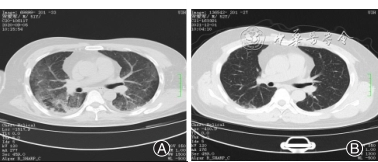

出院后患者自觉肌力逐渐恢复正常,颈部屈伸受限、气促较前好转,偶有双膝关节关节疼痛,全身皮疹没有增加,便自行减少糖皮质激素用量。1个月后(2020年8月31日)患者因咳嗽、咳痰、间断发热再次至湖南省人民医院风湿科住院治疗。体格检查:双肺呼吸音粗,双肺可闻及散在湿罗音,双下肺可闻及velcro啰音,实验室检查:血常规:白细胞计数12.11×109/L,中性粒细胞百分率78.90%,中性粒细胞计数9.56×109/L,单核细胞计数1.21×109/L;CRP 29.86 mg/L;红细胞沉降率20.85;细菌涂片检查:见革兰阳性、阴性球菌;真菌培养:真菌孢子及假菌丝可见;免疫全套、抗心磷脂抗体谱、呼吸道病原体检测、真菌D肽聚糖、抗酸染色检测未见明显异常。胸部CT示:(1)两肺间质性改变;(2)双侧腋窝及纵隔内多发小淋巴结;(3)双侧胸膜增厚(图4A)。入院后立即予以甲强龙(40 mg/d,8 d)并联合用丙种球蛋白(20 g/d,3 d)冲击治疗。入院第3天,患者出现严重的呼吸困难,血气分析:pH 7.42,PO2 55 mmHg,PCO2 64.6 mmHg;血氧饱和度85%~90%之间,考虑患者重症肺炎,呼吸衰竭,病情危重,经知情同意后行持续无创呼吸机辅助通气,并调整抗生素,先后予以头孢曲松、亚胺培兰、氟康唑抗感染,辅以复方磺胺甲恶唑预防卡氏肺孢子菌感染。入院第7天,患者咳嗽、气促较前好转,无创呼吸机辅助通气下血氧饱和度维持在95%~98%,甲泼尼龙调整至25 mg/d,10d。入院第13天,患者在鼻导管吸氧下无呼吸困难,精神状态明显好转,情况好转后给予MTX(10 mg biw)、羟氯喹(0.2 g bid)抑制免疫。第18天,患者好转出院,出院时用等剂量的泼尼松30 mg替代甲泼尼龙,后期门诊随访逐渐减量,治疗期间出现低白蛋白血症、低钾血症、高凝状态等,予以对症处理。

目前,患者规律服用糖皮质激素抗炎及MTX、羟氯喹抑制免疫、阿达木单抗定期皮下注射(40 mg,2周1次)等治疗,现糖皮质激素剂量调整为5 mg,qod,随访1年期间无新发皮疹,肌力基本正常,双肺磨玻璃影逐渐减少(图4B),一般状况可。现患者定期复查,继续风湿免疫科、全科医学科定期随访中。通过文献检索,关于合并MDA5型皮肌炎的报道较少,且既往文献报道MDA5型皮肌炎治疗效果差,本例患者取得了良好的转归。